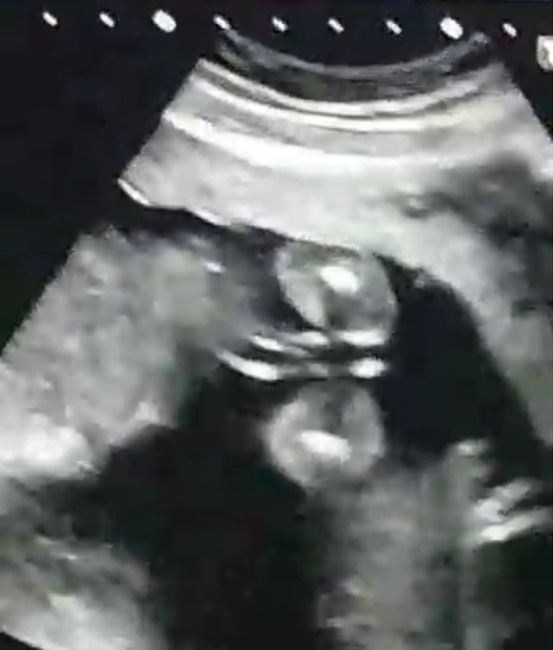

2455 giorni faChe ne dite maschietto o femminuccia? Prima foto TN fatta a 11+3 e la seconda eco normale fatta a 13+3

2488 giorni faSalve bellezze, un po’ d tempo fa pubblicai la foto della mia eco esterna a 8+3 per avere riscontro in qualche opinione, solo che sono più confusa di prima perché tra le mammine eravamo in disaccordo sulla teoria. Ci riprovo ripostandola specificando...